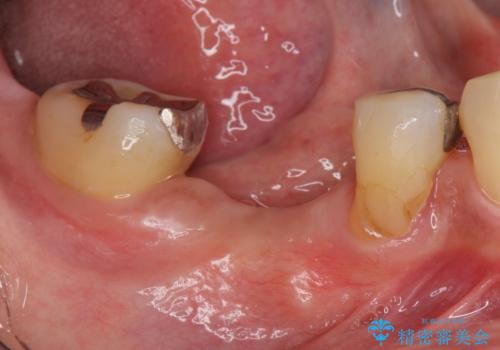

- 歯茎が腫れて痛いとの事で来院。

保存できない状態でしたので抜歯をして歯槽堤保存術を行いました。その後大臼歯部にインプラント治療を行いました。